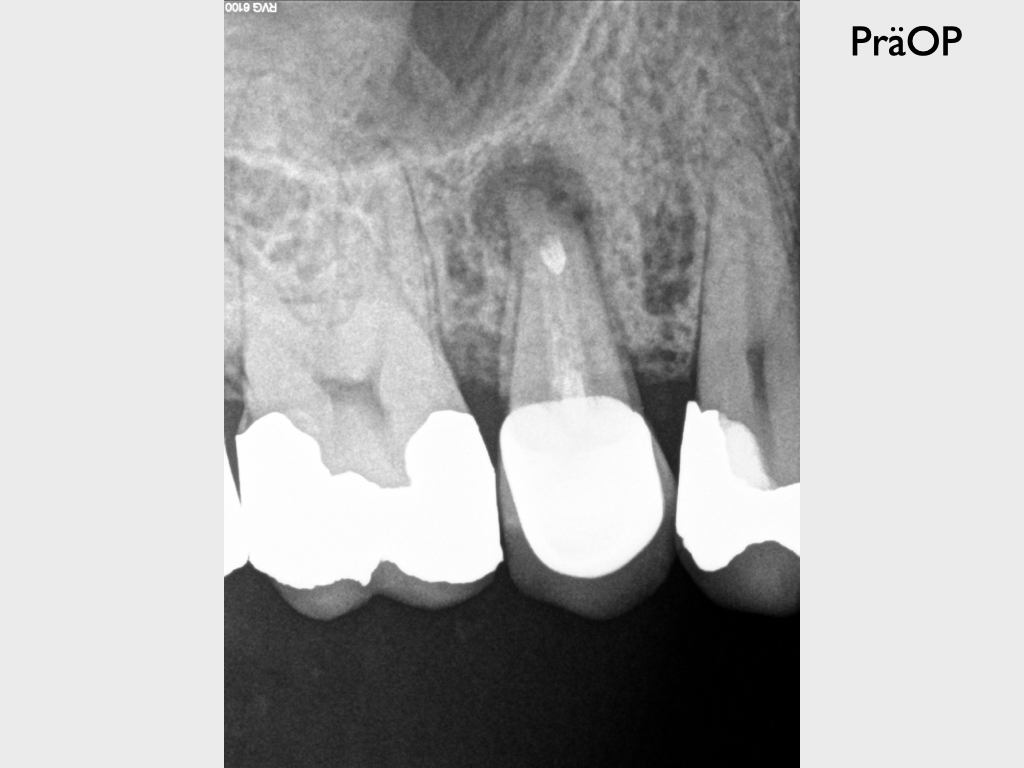

Routine (2)